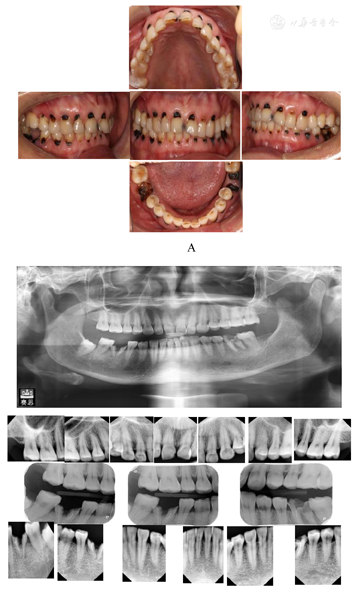

颌面部基本对称,无肿胀畸形。恒牙列,11、12、13、14、15、21、22、23、24、25、31、32、33、34、35、41、42、43、44、45唇颊侧颈部龋坏至牙本质深层,龋坏均达龈下约1 mm;11、21近中邻面累及切角龋坏至牙本质层,均探诊敏感,叩诊(-),冷诊敏感,龈缘充血;36

面约3/4牙体组织龋坏,颊侧龋坏至龈下约1 mm,探诊无感觉,叩诊(-),冷诊无反应,龈无红肿;46牙体龋损至平齐龈缘,呈残根状,探诊无不适、冷诊无反应,叩诊(-),龈无红肿。下前牙舌侧牙结石Ⅰ度,上后牙颊侧牙结石Ⅰ度,牙龈色鲜红,探诊易出血,黏膜色粉红,质柔软,舌体活动自如。前牙深覆

,双侧后牙无完善咬合。全颌曲面断层片及根尖片示:36、46根管内可见高密度根充物影像,根尖区未见明显异常。右侧下颌骨内可见48低位阻生,根周及根尖未见异常。

根据口内检查情况、全颌曲面断层片及根尖片所剑,诊断为11、12、13、14、15、21、22、23、24、25、31、32、33、34、35、41、42、43、44、45深龋,46残根(根管治疗后),36残冠(根管治疗后),48埋伏阻生,慢性龈炎,错颌畸形。